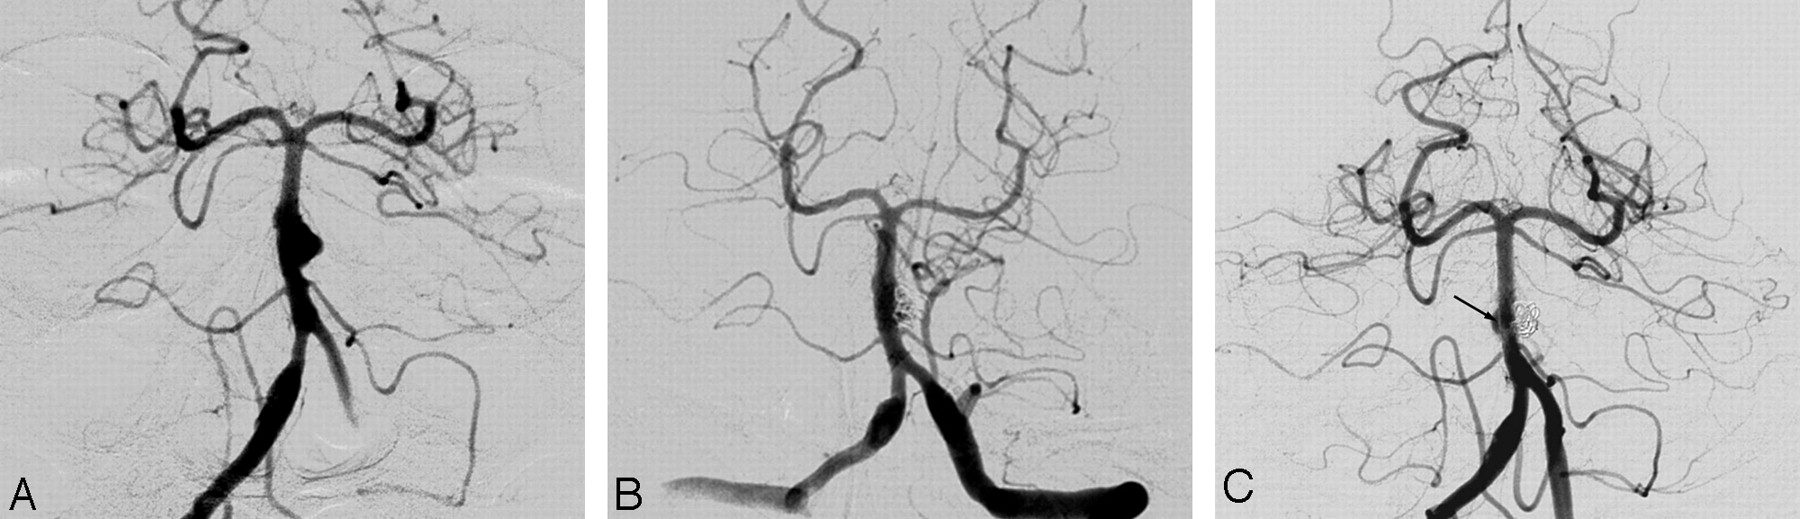

Of the 11 patients with unruptured basilar artery dissection, 2 were initially treated by stent placement. One patient was treated by emergency stent placement for progressive deterioration of consciousness at presentation and near-occlusion of the basilar artery on angiography and completely recovered (Fig 1). The other patient presented with stem compression by a growing pseudoaneurysm 3 years after initial presentation of brain stem infarct (Fig 2). He was treated by double-overlapping stent placement and also completely recovered.

A 42-year-old man presenting with progressive deterioration of consciousness. CT angiogram (A) and vertebral angiogram (B) reveal near-occlusion of the basilar artery by an intramural hematoma (arrows). C, After emergency stent insertion, the basilar artery and left posterior cerebral artery are visualized, but the right posterior cerebral artery is not seen on vertebral angiogram. D, A 2-week (not seen) and 18-month follow-up vertebral angiogram show a patent basilar artery and its branches. The patient had a favorable outcome (mRS score, 0).